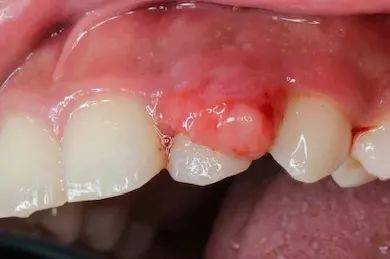

白塞氏病(Behçet's disease)是一种全身性血管炎症性疾病,以复发性口腔溃疡、生殖器溃疡和眼部炎症为典型特征。其表现多样,可能累及皮肤、关节、消化道和神经系统。病因尚不明确,可能与遗传、免疫异常和环境因素(如感染)有关。白塞氏病与扁平苔藓不同,前者更注重系统性症状,而后者主要局限于皮肤和黏膜。